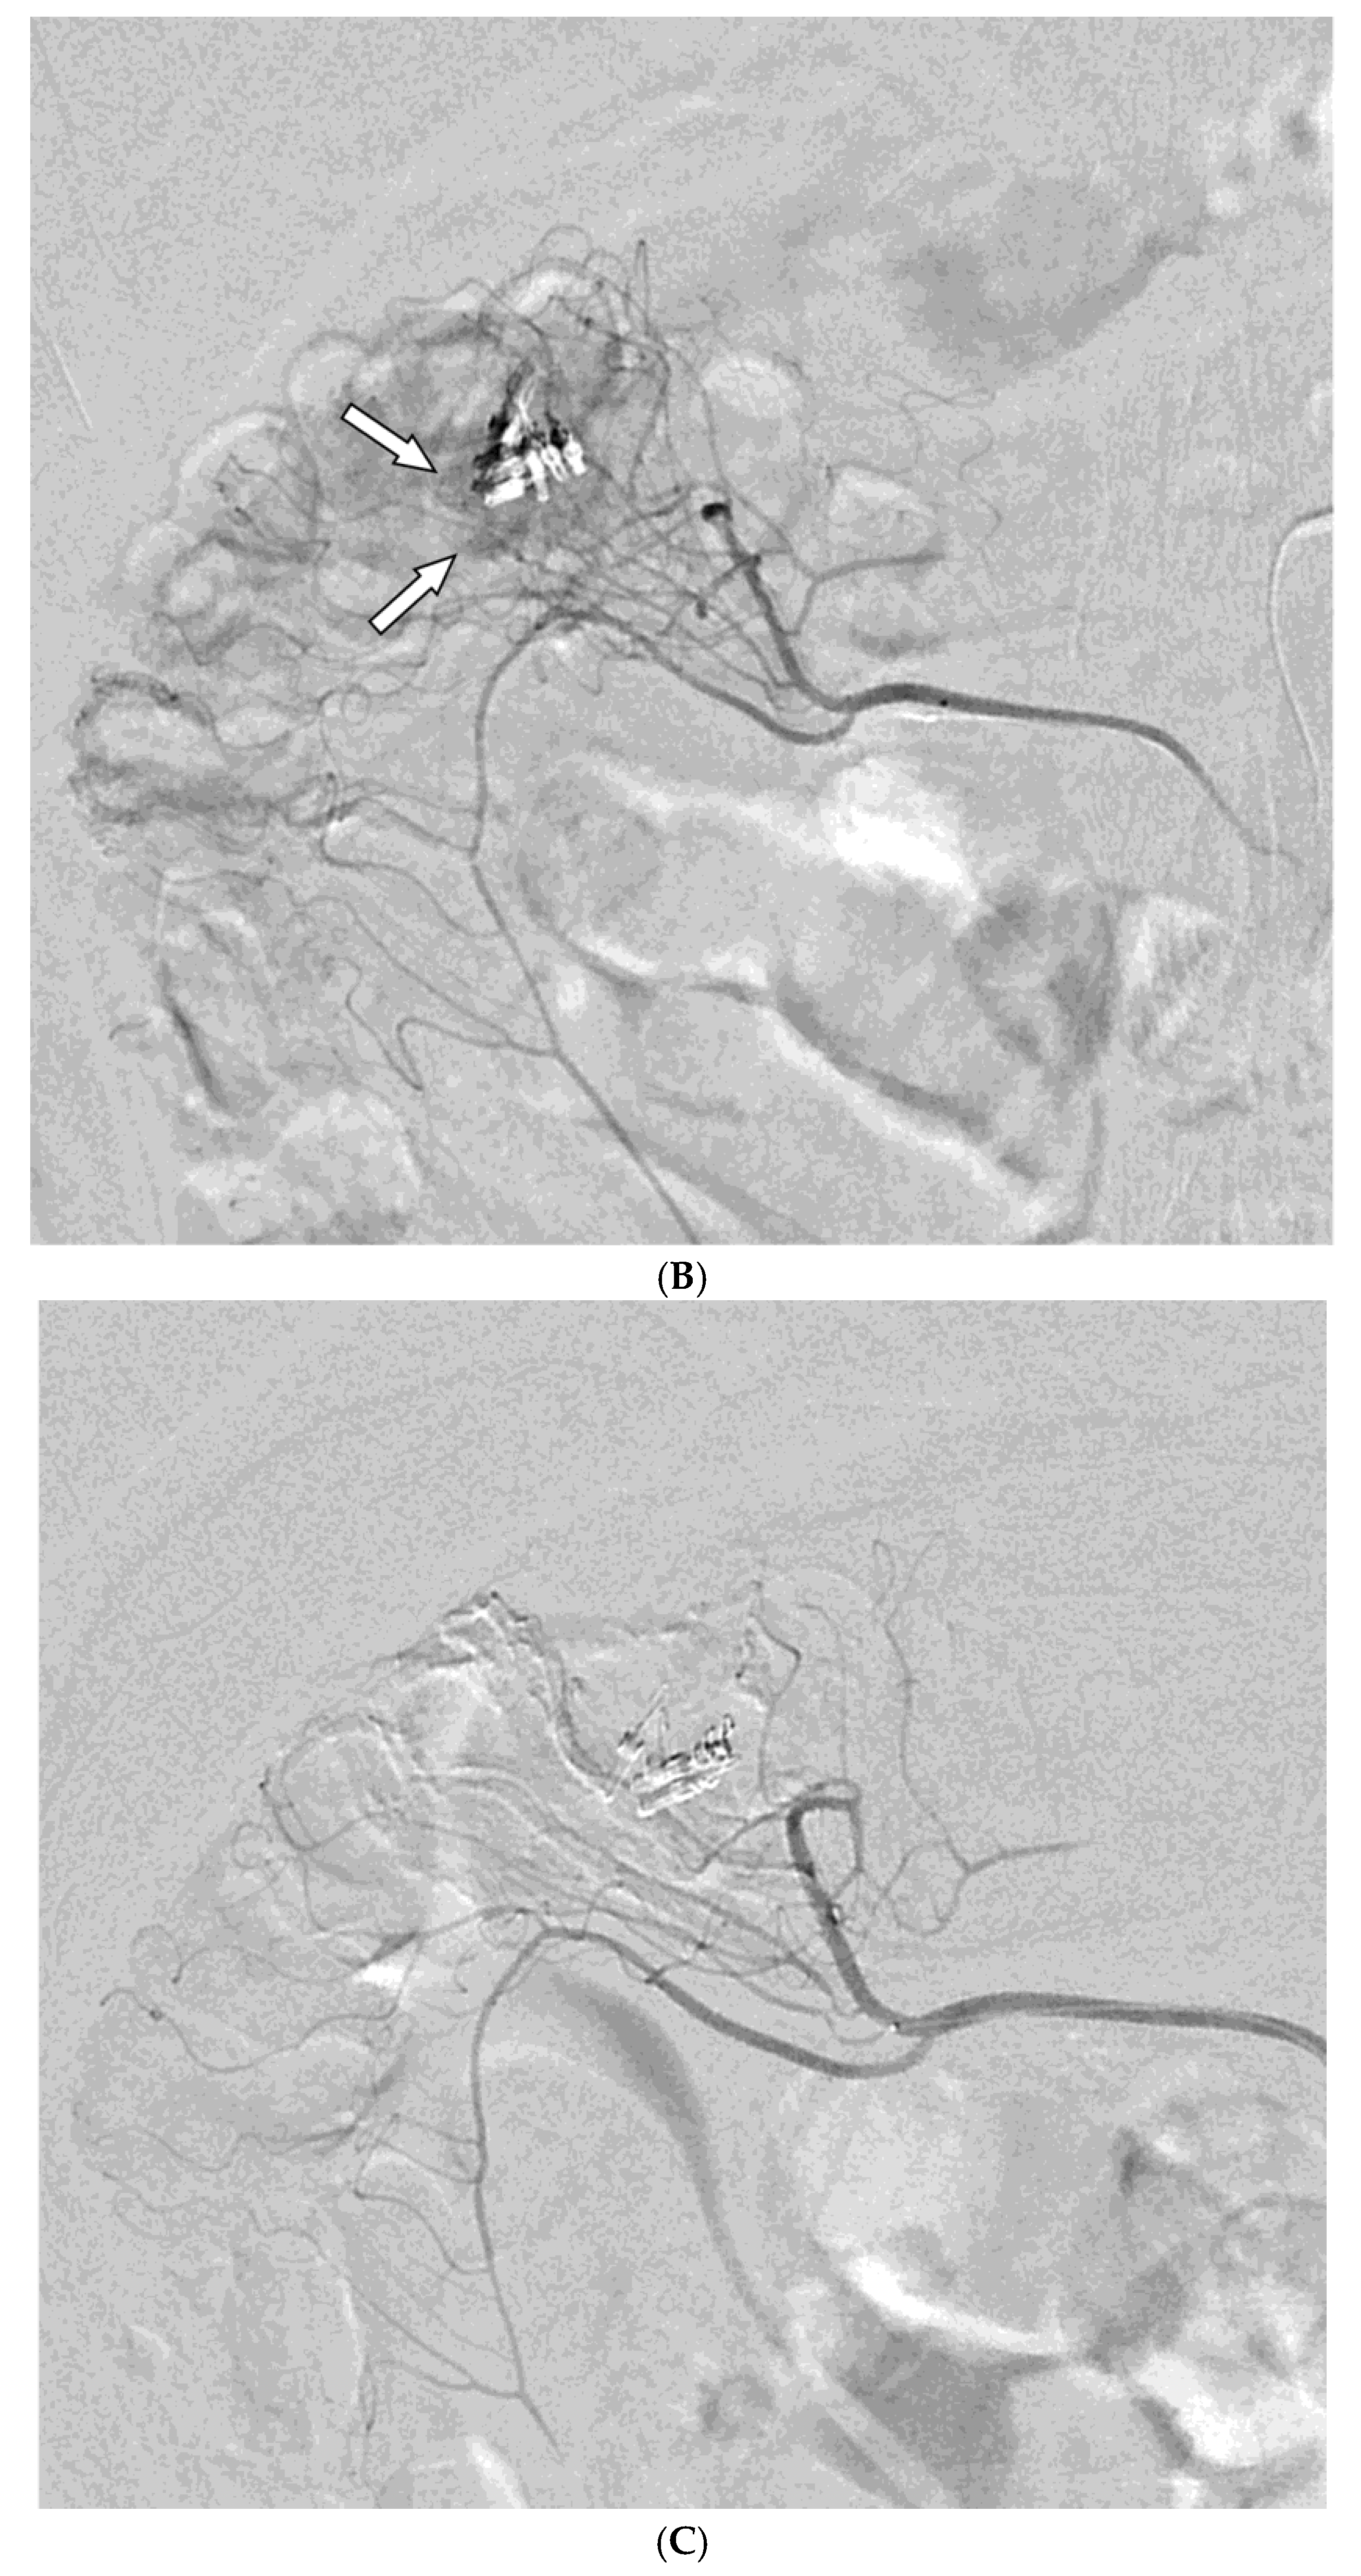

Figure 1. A 78-year-old man presented with hematochezia. (A) Contrast-enhanced axial CT image shows luminal contrast extravasation (arrow) at the ileal loop. (B, C) Selective ileal arteriography shows contrast extravasation (arrows). Due to the distance and tortuosity of the path from the microcatheter tip (arrowheads) to the bleeding focus, superselection was not possible; therefore, embolization was performed using quick-soluble gelatin sponge particles (350–560 µm). (D) Post-embolization arteriography demonstrates that the bleeding focus and the arterial branches leading to it are no longer visible. No further bleeding occurred during the 1-year follow-up.

Among the 29 patients, active bleeding was identified on angiography in six patients (20.7%, 6/29), and tumor staining was observed in two patients (6.9%, 2/29). However, the bleeding focus involved tortuous or small vessels that could not be selectively catheterized; therefore, QS-GSP was administered from a more proximal location (Figure 1 and Figure 2). No evidence of bleeding or tumor staining was detected on angiography in the remaining 21 patients, where the target artery for embolization was determined based on endoscopic and/or CT findings, with angiography serving as a reference (Figure 3).

Embolization was performed on the following arteries: jejunal (n = 7), ileal (n = 7), ileocolic anastomotic (n = 1), cecal (n = 2), colic (n = 7), and rectosigmoid (n = 5). QS-GSPs (150–350 μm, n = 10; 350–560 μm, n = 19) were used as the sole embolic agents in all patients. Angiography following TAE confirmed occlusion or stasis of flow in the target artery in all patients, resulting in a 100% technical success rate.